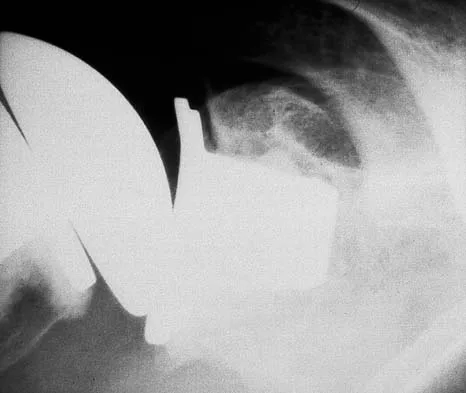

A 52-year-old man who was a former high school pitcher now reports loss of elbow flexion and extension with pain at the extremes of motion. Nonsurgical management has failed to provide relief. Examination reveals movement from 50 degrees to 110 degrees and is painful only at the limits of motion. A radiograph is shown in Figure 12. Treatment should consist of

Based on the history, examination, and radiograph, the patient has typical degenerative arthritis of the elbow. This condition is found almost exclusively in men, and there is almost universally a history of repetitive heavy use or overuse of the elbow. Patients report pain at terminal extension and usually have a flexion contracture. Radiographs reveal osteophytes on the coronoid and olecranon and in the coronoid and olecranon fossae. The osteophytes are often associated with loose bodies that sometimes are attached to the soft tissues. Treatment should consist of removal of all loose bodies and impinging osteophytes using open technique or by arthroscopy. The capsular contractures should be released at the same time. Kasser JR (ed): Orthopaedic Knowledge Update 5. Rosemont, IL, American Academy of Orthopaedic Surgeons, 1996, pp 283-294. Morrey BF: Primary degenerative arthritis of the elbow: Treatment by ulnohumeral arthroplasty. J Bone Joint Surg Br 1992;74:409-413. Redden JF, Stanley D: Arthroscopic fenestration of the olecranon fossa in the treatment of osteoarthritis of the elbow. Arthroscopy 1993;9:14-16.